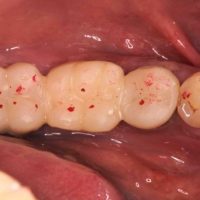

★ 万代総合歯科診療所の集中診療1 時間集中診療 ★

時間集中診療 前回提示したブリッジの片側脱離を起こしてしまった患者さんは、早速治療を受けることになりました。 まずは施術内容を解説致します。 今回は『集中診療』のほうがメインテーマなので、治療の解説は簡単に […]